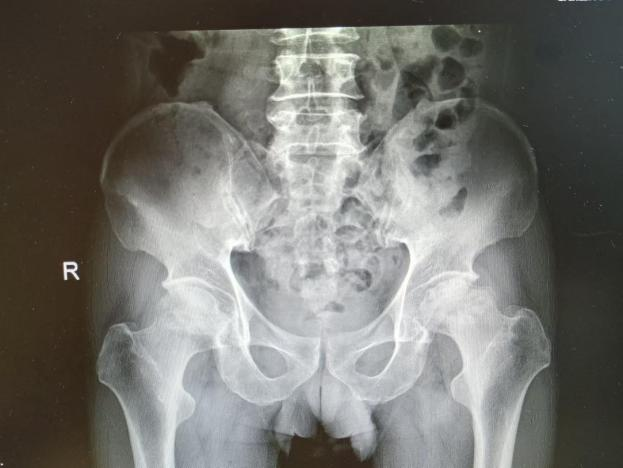

为提升区域内基层医疗机构糖尿病足诊疗服务能力、促进青年医师对糖尿病足的规范化诊治水平,遵义市第二城市医疗集团总院(贵州航天医院)圆满举办贵州省继续医学教育项目——胫骨横向骨搬移技术治疗糖尿病足专题研讨班。 贵州航天医院党委委员、副院长彭亮出席会议并致辞,遵义市第二城市医疗集团各成员单位,以及红花岗区、汇川区、绥阳县、桐梓县等多个区县的基层医疗机构骨干医师参加会议。 研讨班 本次研讨班以胫骨横向骨搬移技术在糖尿病足治疗中的应用为核心主题,围绕糖尿病药物治疗与生活方式管理策略、围手术期血糖精准调控要点、胫骨横向骨搬移技术典型病例深度解析、糖尿病足的临床分型与个体化治疗方案制定等临床实践中的热点与难点展开深入探讨,通过专题授课、案例研讨、互动交流等多元化形式,为参会者搭建了理论与实践结合的学习平台。 此次研讨班不仅为区域内基层医院搭建了学术交流与经验共享的平台,更对推动糖尿病足预防、诊断与治疗的规范化、系统化发展起到了积极作用,有效助力青年医师更新专业知识体系、提升临床技能,为进一步保障区域内糖尿病足患者的健康奠定了坚实基础。 贵州航天医院骨科专家简介 陈明勇 骨一科主任,副主任医师 临床擅长:从事创伤骨科工作约20年,对骨缺损、骨不连、骨肿瘤、肢体畸形等的肢体矫形重建及功能重建,慢性化脓性骨髓炎的根治治疗、糖尿病足的保肢治疗、快速康复理念(ERAS)下的老年骨折的诊治,四肢复杂骨折的诊治,四肢骨折等微创手术治疗具有丰富的临床经验。 2004年毕业于遵义医学院临床专业,曾在中国人民解放军总医院、广西医科大学第一附属医院、上海第六人民医院骨科进修。中国中西医结合学会骨伤科专业委员会横向骨搬移治疗糖尿病足及微血管网再生学组首届委员,遵义市医学会创伤分会常务委员。 瞿 晖 骨科党支部书记,骨二科主任,副主任医师 临床擅长:对骨科的常见病、关节外科、脊柱外科及运动医学疾病的诊治具有丰富的临床经验,熟练掌握骨科手术操作技术。 毕业于遵义医学院临床医学系,2005年前往广州中山大学第一附院骨显微医学部进修学习,2011年前往成都华西医院进修学习,并多次在省内外学习骨科相关知识,是中华医学会骨科分会会员。 赵小锋 中共党员,骨二科副主任,副主任医师 临床擅长:从事骨科临床工作11年,对骨科常见病、多发病诊疗有较为丰富的临床经验,擅长脊柱相关疾病诊断及治疗,尤其是颈、腰、腿疼痛疾病诊断及治疗,擅长胸腰椎骨折微创经皮穿刺内固定术、经皮穿刺椎体成形术、经皮穿刺脊柱内镜下腰椎间盘摘除术、单纯开创腰椎间盘摘除术、腰椎滑脱复位椎间植骨椎融合内固定术、腰椎管狭窄减压融合内固定术及人工髋、膝关节置换术等。 2012年毕业于遵义医学院外科学专业硕士研究生,2019年参加“遵义市115医学人才精英计划”于上海交通大学第一附属医院培训学习,2023年于北京大学第三人民医院脊柱外科进修学习,曾获得遵义市优秀医师荣誉称号。 遵义市手外科第一届委员,遵义市医学会创伤分会第一届委员,遵义市医学会创伤分会第二届委员,贵州省康复医学会第三届脊柱脊髓专业会委员,遵义市医学会烧伤与整形外科学分会委员,发表论文5篇,其中国家级核心期刊1篇,SCI论文1篇,主持市级课题1项并结题,参与市级课题2项。 赵兴东 骨科主任医师 临床擅长:擅长骨科的常见病及各种创伤、四肢骨折创伤修复、骨感染、手足疾病的诊治和手足体表畸形的矫形整复,熟练掌握骨科四肢骨病及创伤的手术操作技术,尤其在四肢关节复杂性损伤、手足外伤、组织缺损创面、难治创面的皮瓣修复方面及平足、高弓足矫形方面及四肢慢性疼痛诊治、康复方面具有丰富的临床经验。 硕士研究生,毕业于遵义医学院临床外科系,2015年前往山东省立医院手足外科进修学习;遵义市医学分会创伤分会第一、二届委员,遵义市手外科医学会第二委届员会常务委员;在省级及省级以上期刊发表文章9篇,参编著作2部,参与主持并完成市级课题1项,参与市级课题2项、省级课题1项。 张艳金 中共党员,骨科副主任医师 临床擅长:从事骨外科工作16年,对复合伤、多发伤的救治、四肢骨干骨折、关节周围骨折、骨肿瘤、骨髓炎等诊治具有丰富的临床经验。 中共党员,硕士研究生,2006年本科毕业于山西医科大学第二临床医学院,2011年研究生毕业于北京军区总医院;在“老年COPD患者合并髋部骨折的诊治”国际合作课题组研究两年,在老年髋部骨折的诊治方面具有丰富的经验,并发表论文6篇;主持遵义市级课题1项,承担遵义医科大学的临床教学工作,获得遵义医科大学优秀带教老师荣誉。编撰有《骨科疾病诊疗精粹》一书,开展2项新技术,编撰地方规范《务川自治县创伤骨科常见疾病诊疗规范》一书。 张俊凯 骨科副主任医师 临床擅长:从事骨科临床工作28年,对创伤骨折、骨感染、骨缺损、骨不连等外科诊治,四肢骨折的微创手术治疗,四肢复杂骨折(如关节内粉碎性骨折、多发骨折等)的损伤控制及手术治疗等具有丰富的临床经验。 1995年毕业于遵义医学院临床专业,2009年前往复旦大学附属医院骨科进修1年。 卢懿明 中共党员,骨科副主任医师 临床擅长:从事骨科工作18年,对创伤骨折、四肢骨折的微创手术治疗、四肢复杂骨折(如关节内粉碎性骨折、多发骨折等)的损伤控制及手术治疗,尤其是髋部骨折的PFNA等微创技术,踝关节骨折、膝关节周围骨折的Mipo微创技术等具有丰富的临床经验,开展了4项新技术,发明6项新型专利技术。 2005年毕业于遵义医学院临床专业,2017年,前往南方医科大学第三附属医院骨科进修半年,回院后运用Mipo技术对骨干骨折及干骺端骨折的治疗技术,同时积极开展骨盆骨折、髋臼骨折腹直肌外侧切口的应用;发表了多篇专业论文,经常参与省内外学术交流会授课,获得医院荣誉称号多个。 邬夏荣 骨科副主任医师 临床擅长:从事骨科工作16年,对四肢复杂骨折、骨肿瘤的诊治,尤其是足踝创伤、慢性踝关节损伤、平足症等诊疗具有丰富的临床经验。 2006年毕业于遵义医科大学临床医学专业,曾在陆军军医大学西南医院进修学习,发表多篇骨科学术论文。 余德怀 中共党员,骨科副主任医师 临床擅长:从事骨科工作10余年,对运动医学、骨关节、脊柱外科常见病、多发病的诊治具有丰富的临床经验。 硕士研究生,2011年毕业于遵义医学院临床医学专业,曾前往遵义医科大学附属医院运动医学专业进修学习;是贵州省医学会运动医学分会青年委员,西部关节镜联盟委员;发表多篇骨科学术论文。 冯 乾 骨科副主任医师 临床擅长:从事骨科工作近20年,熟练掌握骨科多发病及常见病的诊治,尤其对脊柱退变性疾病的诊断及治疗具有丰富的临床经验,主要研究脊柱微创相关治疗方式,能熟练开展椎间孔镜及UBE。 曾前往北京大学第三医院进修学习疼痛及椎间孔镜、首都医科大学友谊医院专业进修脊柱内镜;是贵州省康复医学会第三届脊柱脊髓专业委员会委员;发明专利3项、发表脊柱外科专业论文多篇。 贵州航天医院骨科简介 基本情况 贵州航天医院(原3417医院)骨科组建于1968年,前身是以创伤和断肢(断指)再植闻名于世的上海市第六人民医院骨科,中国断肢(断指)再植的奠基者、中科院院士陈仲伟等专家莅临科室指导医疗和教学,并在70年代开展了贵州省首例断肢(断指)再植手术。组建50余年来,诊治患者已逾百万,挽救了无数的伤病员,成为了保障遵义地区人民群众健康的重要支撑。 经过几代人的不懈努力,今天的骨科,已由创伤骨科发展至骨病、骨肿瘤、骨结核等领域,现有脊柱外科、关节外科、四肢创伤、手足外科四个亚专科,成为了集医疗、教学、科研于一体的综合学科,是贵州省临床重点专科、遵义市临床重点专科、遵义市骨科临床医学中心、遵义市基层骨科专科联盟理事长单位。 科室目前开放床位110张,共有医护人员50余人,副高级以上专家18人,硕士研究生15人。拥有一流骨科医疗设备多台,每年不定期选派优秀技术骨干到全国各大知名医学院校进修、学习、参观、交流,并邀请国内、国外知名专家教授来院进行交流、指导,通过不断引进国内外先进的诊疗技术,科室医疗技术水平稳步提升,为广大人民群众提供了优质的医疗服务。 专科特色 骨一科 (一)骨缺损、骨不连的肢体与功能重建 胫骨横向骨搬移技术治疗糖尿病足: (二)慢性骨髓炎的根治治疗 (三)肢体缺血性疾病如糖尿病足、脉管炎的保肢治疗 (四)皮瓣修复 (五)复杂创伤的治疗 (六)老年髋部骨折及小儿骨折快速手术 老年髋部骨折: 骨二科 (一)胸腰椎骨折微创经皮椎弓根螺钉固定术 (二)老年性骨质疏松性患者腰椎滑脱脊柱内固定术(骨水泥螺钉) (三)V形双通道脊柱内镜技术(VBE)腰椎融合术治疗腰椎退行性疾病 (四)老年性骨质疏松性骨折(PVP/PKP)术 (五)人工髋关节置换术 (六)双侧股骨头坏死人工全髋关节置换 (七)右侧全髋置换术后假体周围骨折翻修 (八)人工膝关节置换术 (九)人工膝关节假体松动翻修 (十)关节镜技术 传统手术切口 关节镜技术切口 诊疗范围 骨一科 1.四肢创伤、矫形。 2.手、足踝外科。 骨二科 End